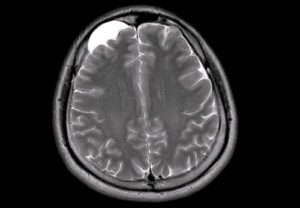

Картина арахноидальных изменений ликворокистозного характера в ходе исследований МР и КТ показывает наличие очагов с плотностью цереброспинальной жидкости, что подтверждает кистозную, неопухолевую природу образования.

Чаще всего диагноз «арахноидальные изменения ликворокистозного характера» пишется тогда, когда на МРТ достоверно не видно никаких кист, а имеется просто неравномерное расширение субарахноидального пространства, то есть увеличение количества спинномозговой жидкости (ликвора) между мозгом и костью черепа.

Основным методом ее диагностики является МРТ. На снимках арахноидальные изменения ликворокистозного характера выглядят как образования темного цвета, с четко ограниченными контурами, чаще всего округлой формы.